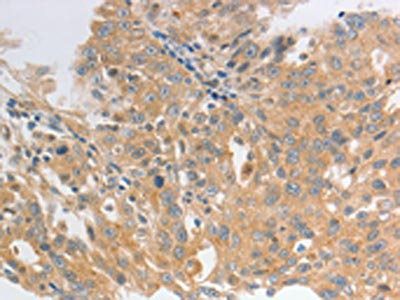

The image on the left is immunohistochemistry of paraffin-embedded Human lung cancer tissue using CSB-PA562577(HCRTR2 Antibody) at dilution 1/50, on the right is treated with synthetic peptide. (Original magnification: ×200)